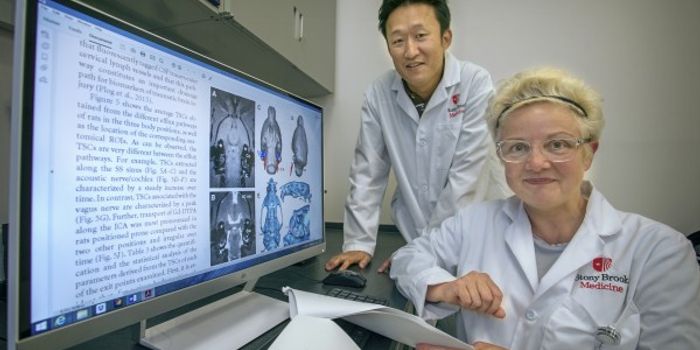

JUN 15, 2020Cell & Molecular BiologyThe autonomic nervous system is linked to the intrinsic cardiac nervous system (ICN), which is thought to help regulate ...